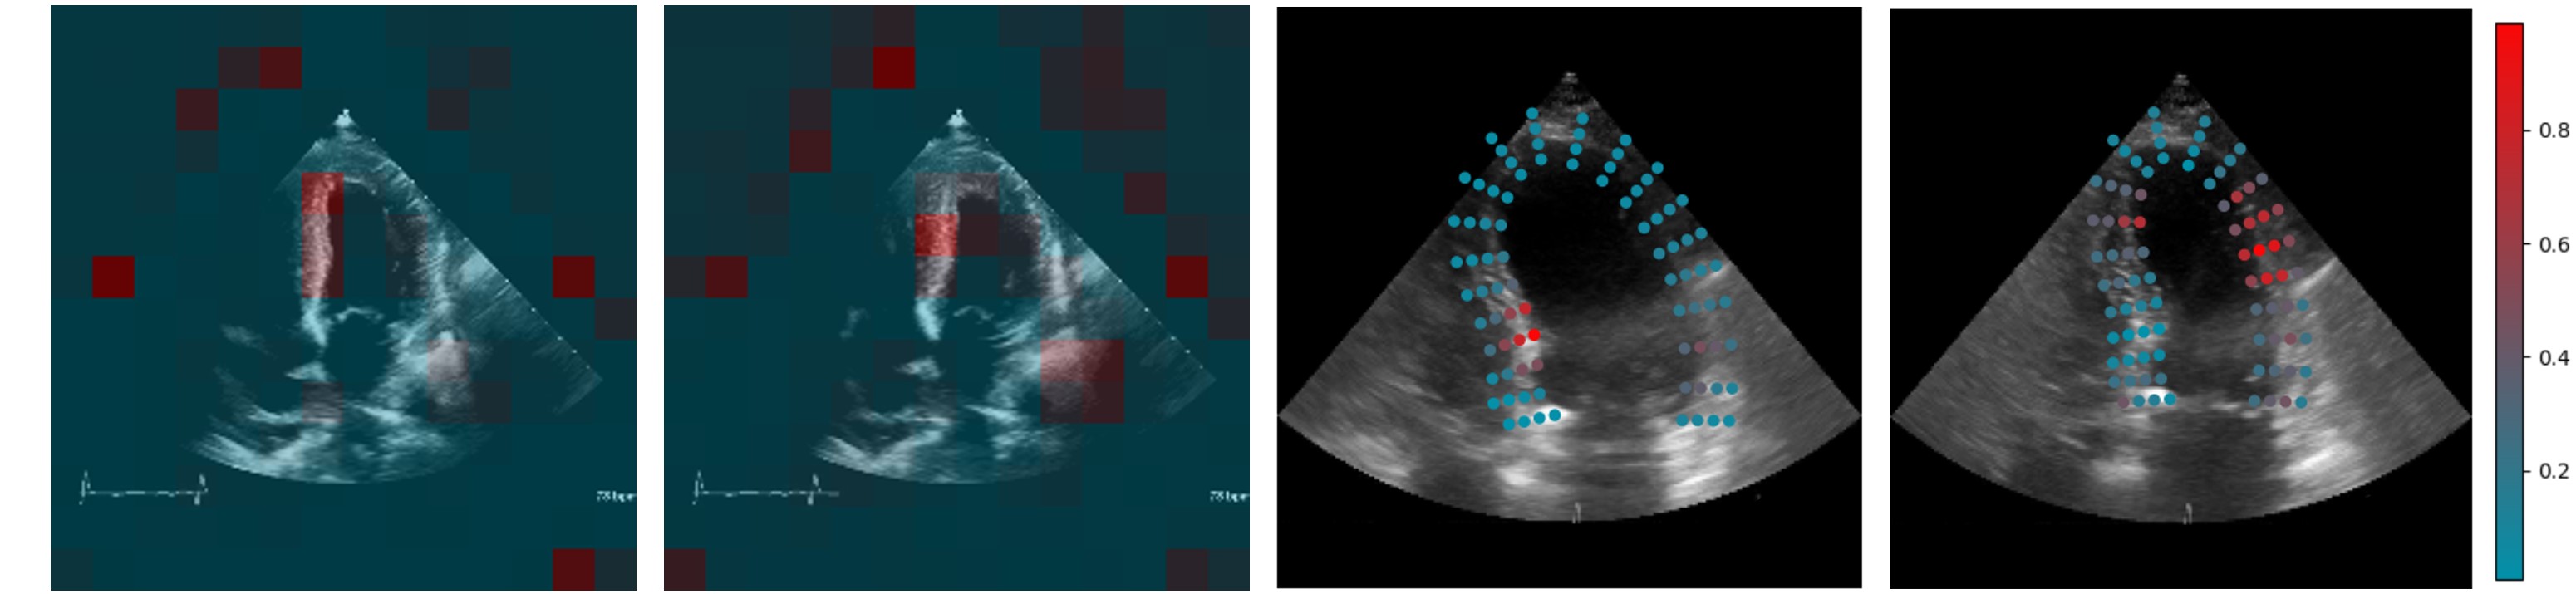

Refer to caption

Figure 5: Left: attention maps from a ViViT. Right: points from a ViACT, colored with attention map. Attention maps are from a single head belonging to the class token of the final frame encoder transformer block and normalized.